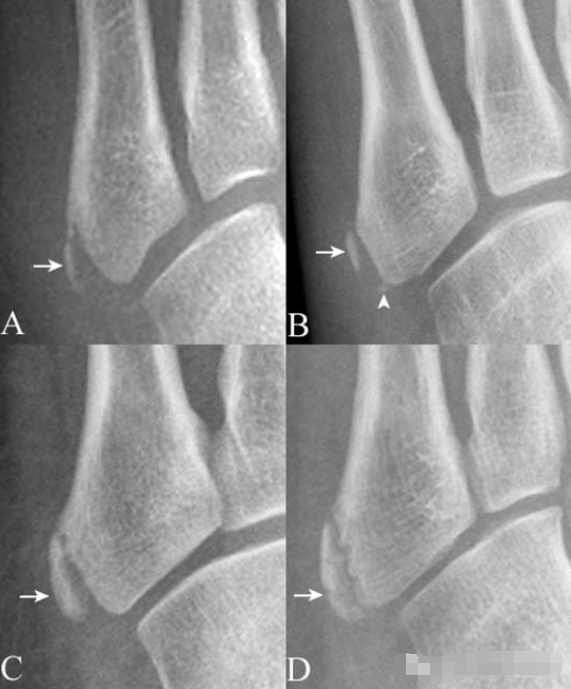

4.跟骨上副骨:呈跟骨上方、三角骨(白箭头)后方骨性结节(箭),为正常变异。腓骨副骨(黑箭头)与距骨重叠。